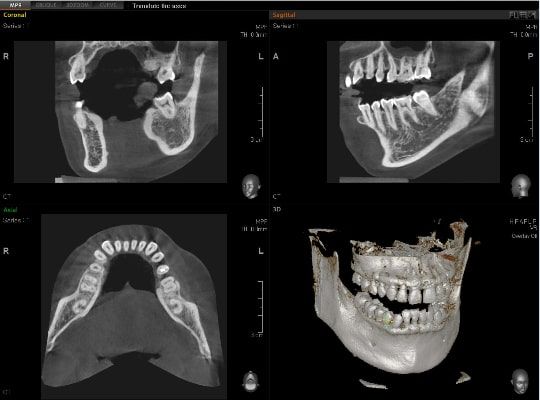

El innovador FOV proporciona un volumen en forma de arco que muestra una vista más amplia de la dentición en comparación con otros dispositivos del mismo FOV.

Normalmente, una imagen de 10x8.5 muestra el diente No.8. Sin embargo, cuando los terceros molares están tumbados sobre su lado hay una gran posibilidad de que el diente se corte de la imagen.

El “volumen en forma de arco” elimina esta posibilidad y muestra el área de dentición oculto.